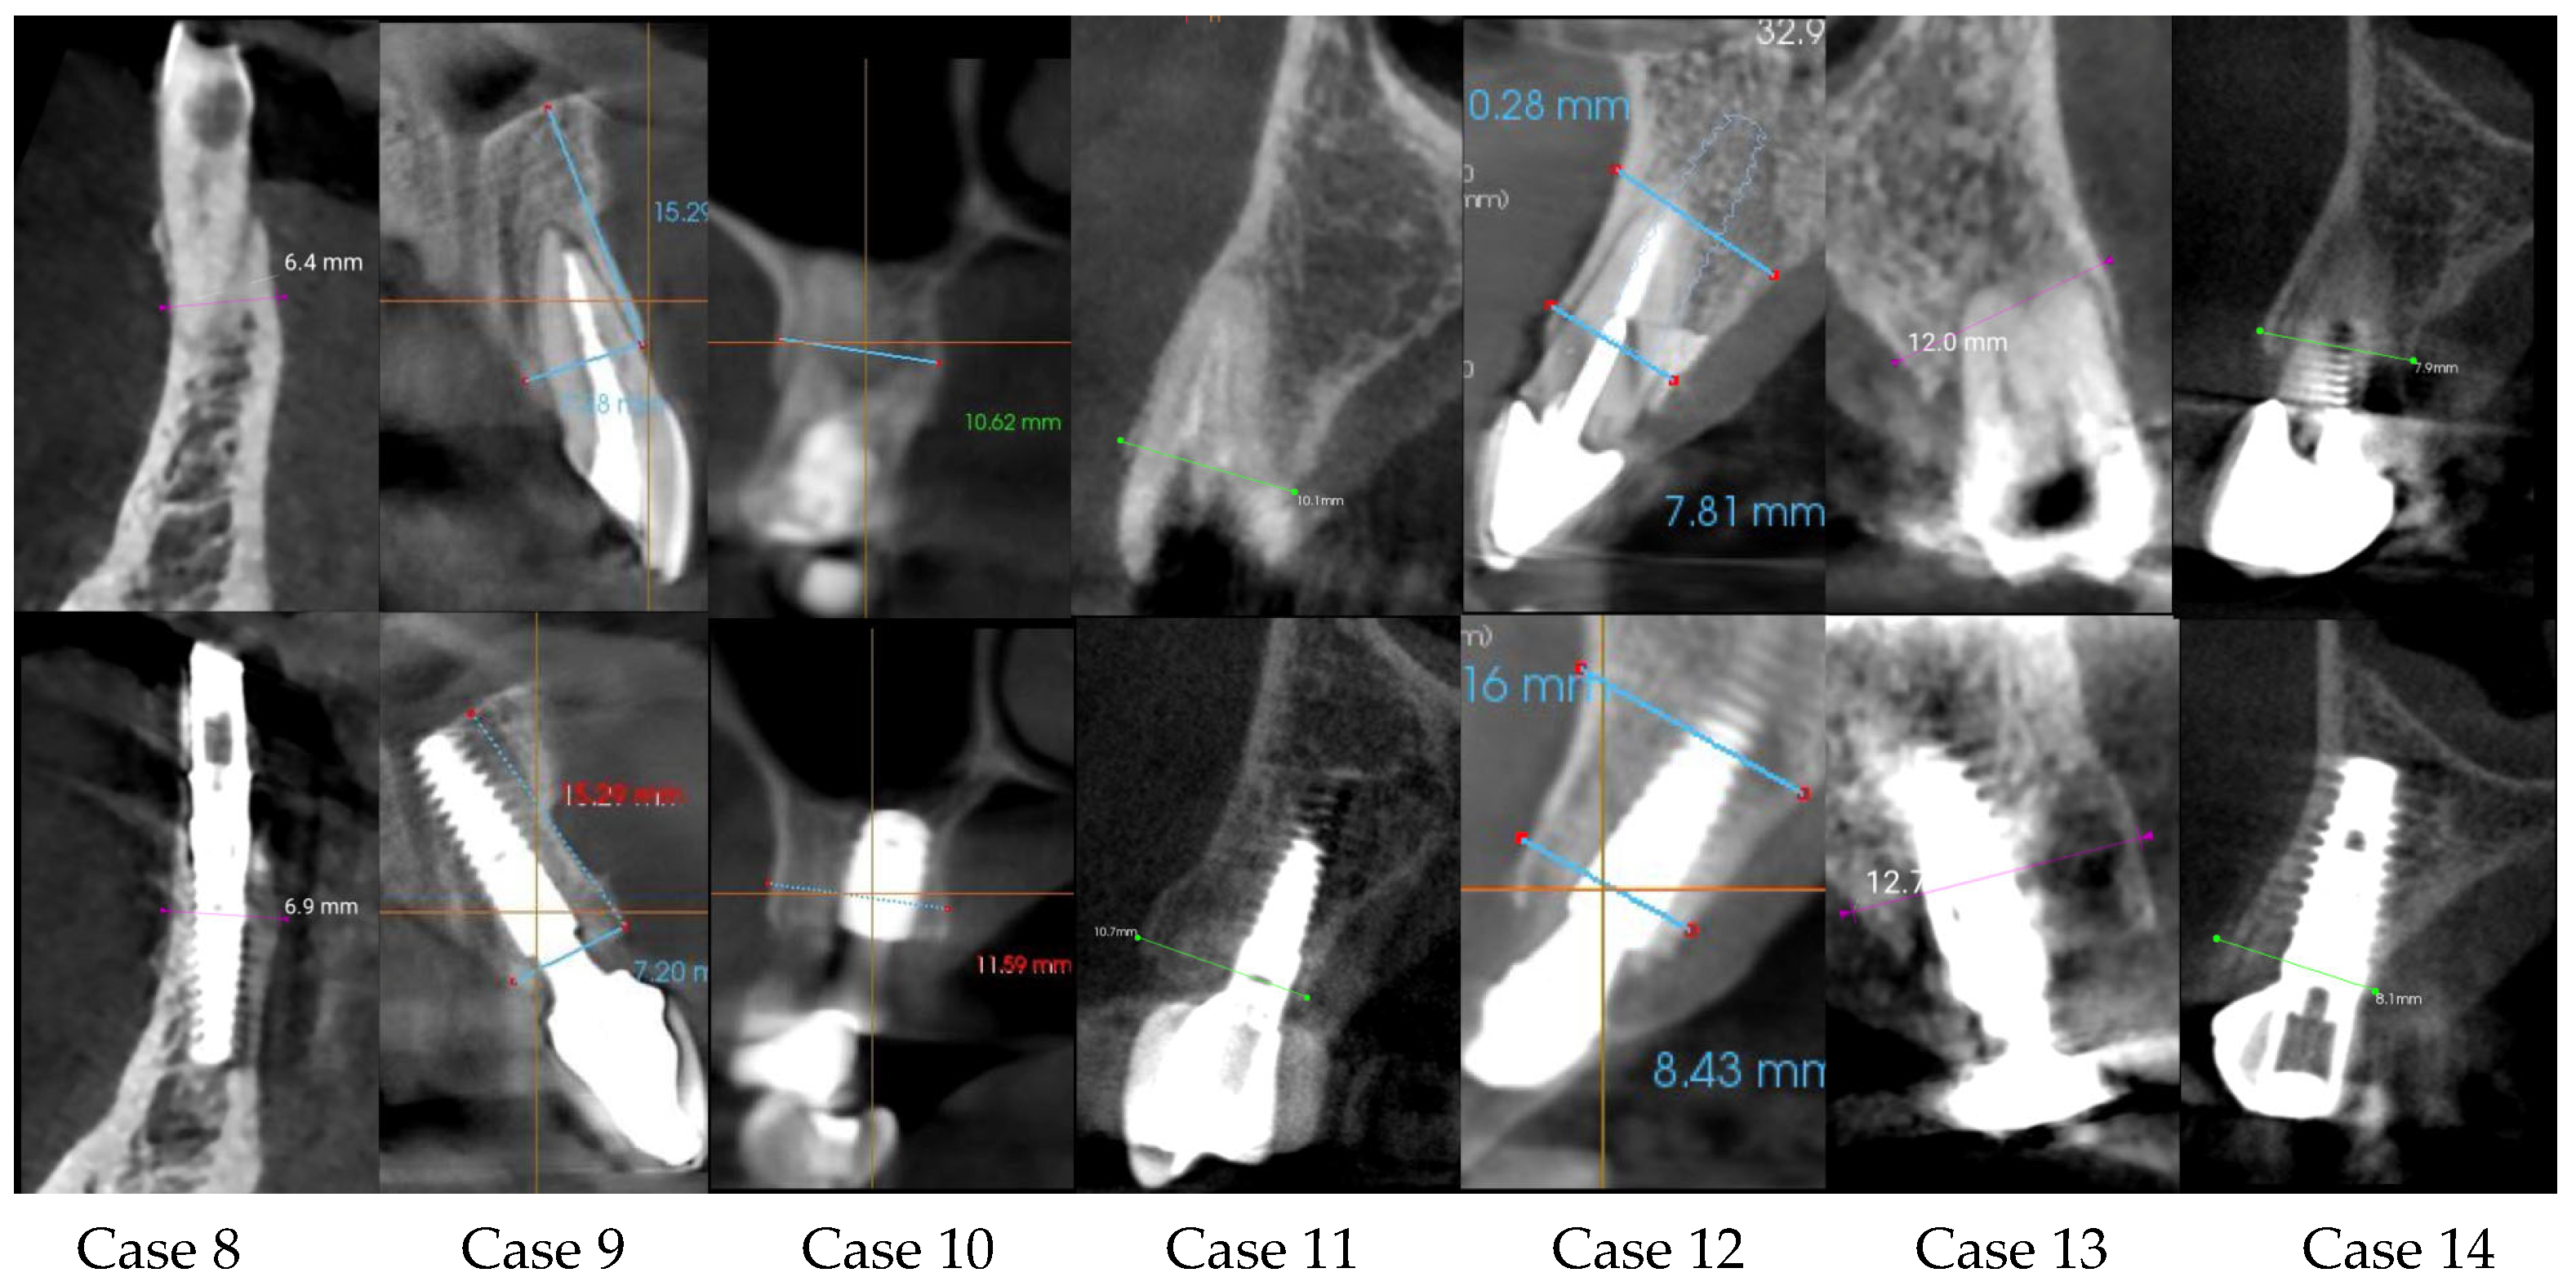

| Center/Case | Sex/Age | Tooth Number | Ridge Thickness before (mm) | Ridge Thickness after (mm) | Follow-Up Time | Difference | Immediate Loading |

|---|---|---|---|---|---|---|---|

| C2 case 8 | Male/68 | 42 | 6.40 | 6.90 | 6 months | 0.50 | yes |

| C3 case 9 | Male/62 | 21 | 7.18 | 7.20 | 8 months | 0.02 | yes |

| C3 case 10 | Male/58 | 17 | 10.52 | 11.69 | 5 months | 1.17 | yes |

| C1 case 11 | Male/68 | 24 | 10.10 | 10.70 | 6 months | 0.60 | yes |

| C3 case 12 | Female/46 | 11 | 7.81 | 8.43 | 7 months | 0.62 | yes |

| C2 case 13 | Male/77 | 24 | 12.00 | 12.70 | 6 months | 0.70 | yes |

| C1 case 14 | Male/74 | 13 | 7.9 | 8.1 | 4 months | 0.20 | no |

| Before | After | p-Value | ||

|---|---|---|---|---|

| Ridge thickness (mm) | 14 | 8.4 ± 1.8 | 9.0 ± 2.0 | p < 0.0001 |